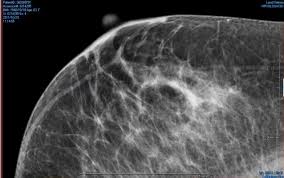

What Does Cancer Look Like On Mammogram : Mammography 3d Mammography Tomosynthesis Densebreast Info Inc / The rate of breast cancers discovered as dcis is thought to be increasing, but this is partially a testament to the effectiveness of mammographic breast cancer screening programs.ductal carcinoma in situ represents up to 30% of all new cases of breast cancer discovered by breast cancer screening.. Regular mammograms are the best tests doctors have to find breast cancer early, sometimes up to three years before it can be felt. In this mammogram image, the breast calcifications are in ductal patterns. Any area that does not look like normal tissue is a possible cause for concern. Calcifications are tiny flecks of calcium — like grains of salt — in the soft tissue of the breast that can sometimes indicate the presence of an early breast cancer. Any area that does not look like normal tissue is a possible cause for concern.

Abnormalities such as cancerous tumors usually appear brighter because they are denser. In this mammogram image, the breast calcifications are in ductal patterns. Dr sarah jarvis mbeif a mammogram is abnormal, further tests will be needed. Breast cancer and some noncancerous (benign) breast conditions can appear white on a mammogram. You may notice dimpling or pitting, and the skin on your breast.

Invasive breast cancer can appear as a white patch or mass on a mammogram. The tumor cells don't stay within the clear borders of the mass, but instead invade the nearby breast tissue. You may notice dimpling or pitting, and the skin on your breast. A rash isn't the only visual symptom of inflammatory breast cancer. Regular mammograms are the best tests doctors have to find breast cancer early. In a normal breast, a mammogram shows normal skin dark grey fat and lighter grey breast tissue. According to the american cancer society (acs), the most common sign of breast cancer is a new lump or mass in the breast. How can mammograms be used? Cancers may be seen as masses (like a ball, but usually with an irregular shape), areas of asymmetry that resemble normal tissue, calcifications (white specks), and/or areas of architectural distortion (imagine the puckering caused by pulling a thread in a piece of fabric). In this mammogram image, the breast calcifications are in ductal patterns. Healthy mammograms can still vary in appearance. It is important to bear in mind that most women who are asked to come back after. Any area that does not look like normal tissue is a possible cause for concern.

Invasive breast cancer can appear as a white patch or mass on a mammogram. Often, you might not feel a lump, even if it is there. Regular mammograms are the best tests doctors have to find breast cancer early, sometimes up to three years before it can be felt. The appearance of normal breast tissue on a mammogram varies from person to person, and no two mammograms look the same. Mammograms provide a look inside the breast to help doctors (radiologists) detect breast cancer, often in the early stages when it's most treatable.

This is considered an abnormal mammogram, but not necessarily one that's indicative of cancer. The tumor cells don't stay within the clear borders of the mass, but instead invade the nearby breast tissue. The appearance of normal breast tissue on a mammogram varies from person to person, and no two mammograms look the same. Dr sarah jarvis mbeif a mammogram is abnormal, further tests will be needed. The doctor reading your mammogram will be looking for different types of breast changes, such as small white spots called calcifications, larger abnormal areas called masses, and other suspicious areas that could be signs of cancer. Regular mammograms are the best tests doctors have to find breast cancer early, sometimes up to three years before it can be felt. Mammograms will often detect areas that are more dense than normal breast tissue or that have little flecks of calcium within milk ducts. What does breast cancer look like on a mammogram? What does breast cancer look like on a mammogram? You may notice dimpling or pitting, and the skin on your breast. This can make it harder for your radiologist to spot signs of breast cancer, since dense tissue and tumors both look white in mammogram images. Any area that does not look like normal tissue is a possible cause for concern. Any area that does not look like normal tissue is a possible cause for concern.